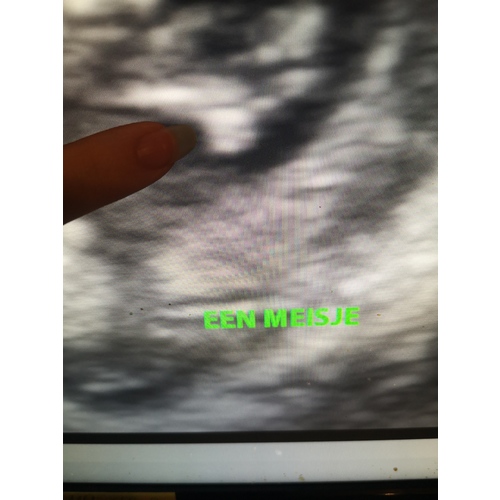

Die van mij zoekt echt tussen de beentjes, en dan is het ook echt wel duidelijk maar het is niet makkelijk daar zen goed beelt op te krijgen als ze niet meewerken 🙈 ik weet niet of jullie het goed gaan zien op deze foto, maar aan mijn vinger zou je 3 streepjes onder elkaar moeten zien allemaal even lang. Dat zijn dan de buitenste (2 strepen) en de binnenste( middelste streep) schaamlippen. En bij een jongen ja dan zie je daar wat hangen ea 🙈

Ik heb ingezoomd dus normaal is dat veeeeel kleiner op je echo foto is echt wel even weten waar j emoet kijken, gelukkig legt de gyn dat allemaal uit met hun getrainde ogen zien die dat onmiddellijk 🙈